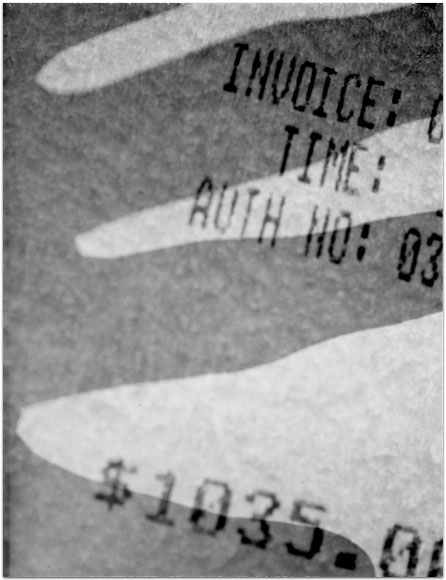

- Itis

- 2004

- 3.25″ × 4.25″

- Photographic montages of my hands & health paraphernalia on Polaroid Type 664 & 669 Film using a Daylab Printer.

- Frustrated by a lack of mobility and severe pain with my fingers, unable to accomplish any task requiring joint dexterity,

I noticed piles of health related papers strewn around. I layered these in a slide printer without removing

my hands, enlarging both onto the film.